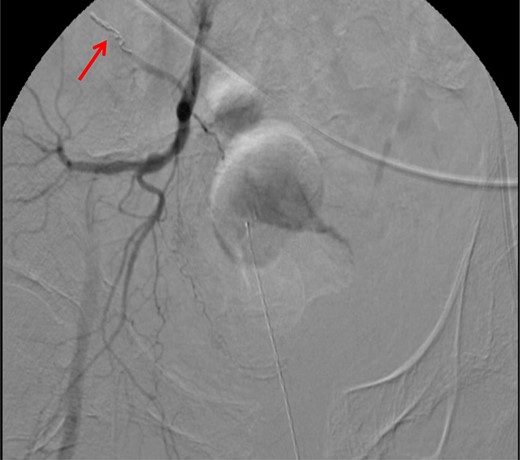

CT abdomen/pelvis with contrast was performed and a blush of contrast was noted posterior to the right pubic bone. Prior to taking patient for exploratory surgery, he was transferred to the interventional radiology suite where a pelvic angiogram was performed revealing an abnormal blush localized to the distal branches of the right iliolumbar artery (Fig. 2). Delayed phase of the angiogram demonstrated early venous filling consistent with a traumatic arteriovenous fistula which was embolized with 300–500 µ of embospheres and three 3 × 2 microcoils (Figs 3 and 4).

CT angiogram delayed phase of angiogram shows early venous filling consistent with AV fistula.